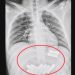

İlk müdahalesi yapılan Almira, ambulansla kaldırıldığı Van Yüzüncü Yıl Üniversitesi Dursun Odabaş Tıp Merkezi’nde hekimlerin tüm eforuna rağmen kurtarılamadı.